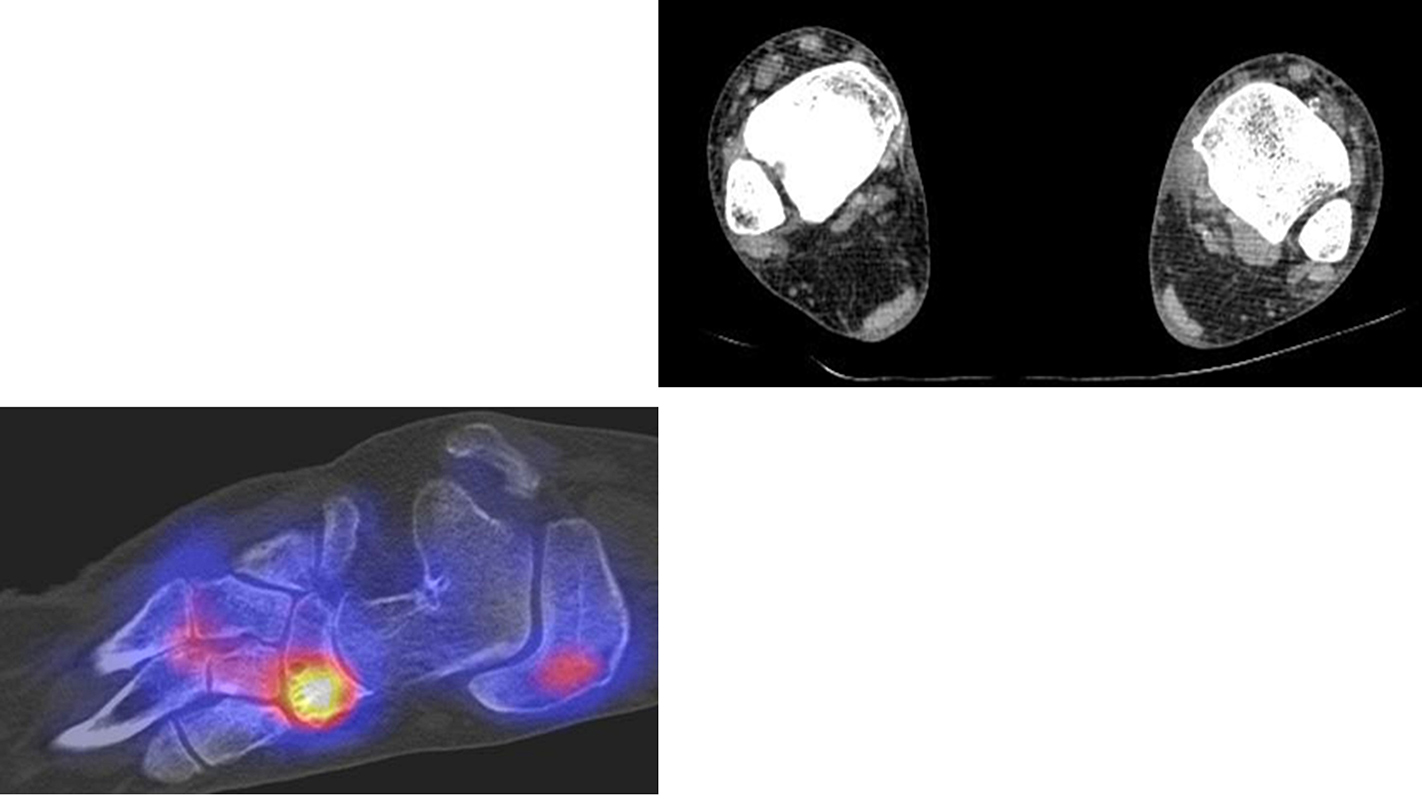

Die Abbildungen 4.2.a bis d zeigen den typischen Aspekt einer talacalcanearen Coalitio. Es besteht nur eine linksseitige, symptomatische Coalitio talocalcaneare (4.2.a und c); das 35 Tage zuvor angefertigte MRT zeigt keine auffälligen Signalveränderungen (4.2.b und d).